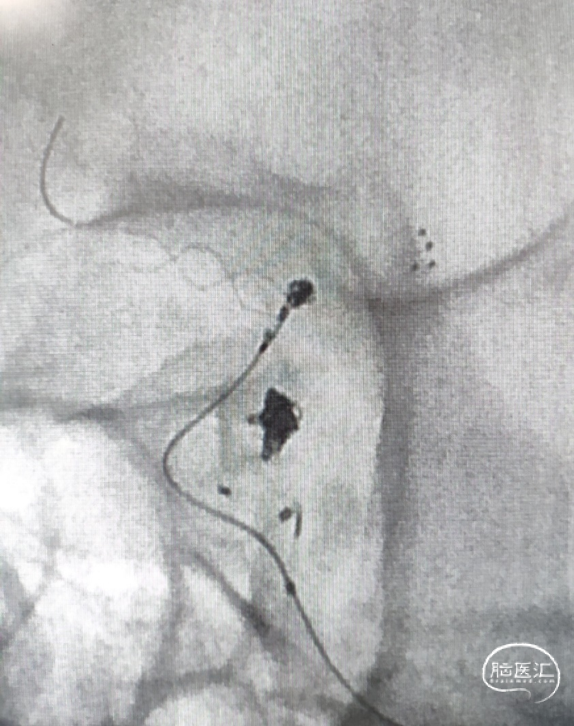

手术方案:穿网眼释放LEO+Baby支架与一期释放的支架形成T型,辅助弹簧圈栓塞。

1. 以Seldinger技术经右侧股动脉穿刺,造影后选取工作位并建立路径图。

2. 穿Solitaire支架网孔,将支架微导管及弹簧圈微导管分别超选到位。

3. 支架半释放后填圈。

支架微导管及弹簧圈微导管到位。

支架释放后,送入首枚2*4 2D的弹簧圈栓塞动脉瘤。

支架全释放。

支架全释放后送入第二枚1.5*2-2D弹簧圈。

术后造影显示动脉瘤致密栓塞,各分支血管血流通畅。

术后双容积成像显示支架头端完全覆盖动脉瘤瘤颈,并且与Solitaire支架形成“Kissing”,“T型”形成。